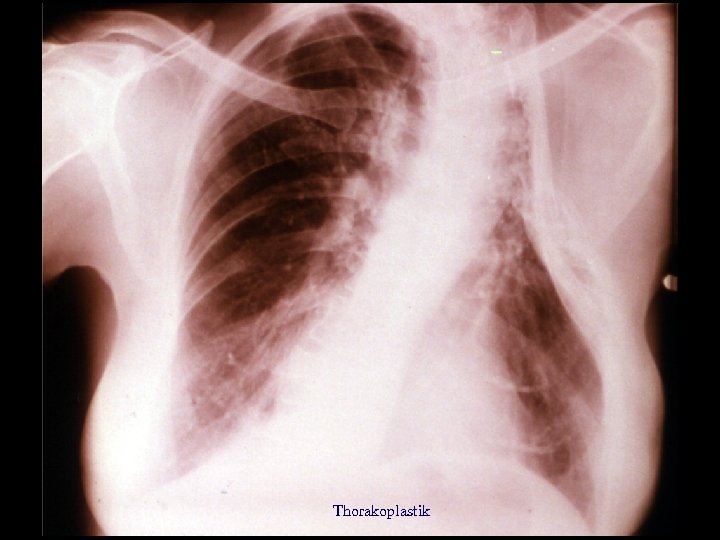

Liegekur (2) • Messung der Temperatur sechs mal am Tag. • Genaue Ernährungsvorschriften. • Der Sanatoriumsaufenthalt dauerte zwischen wenigen Monaten bis mehrere Jahre. • Nach 1910 Einführung der Pneumothoraxbehandlung. • Später Thorakoplastik und Paraffinplombe.

Thorakoplastik